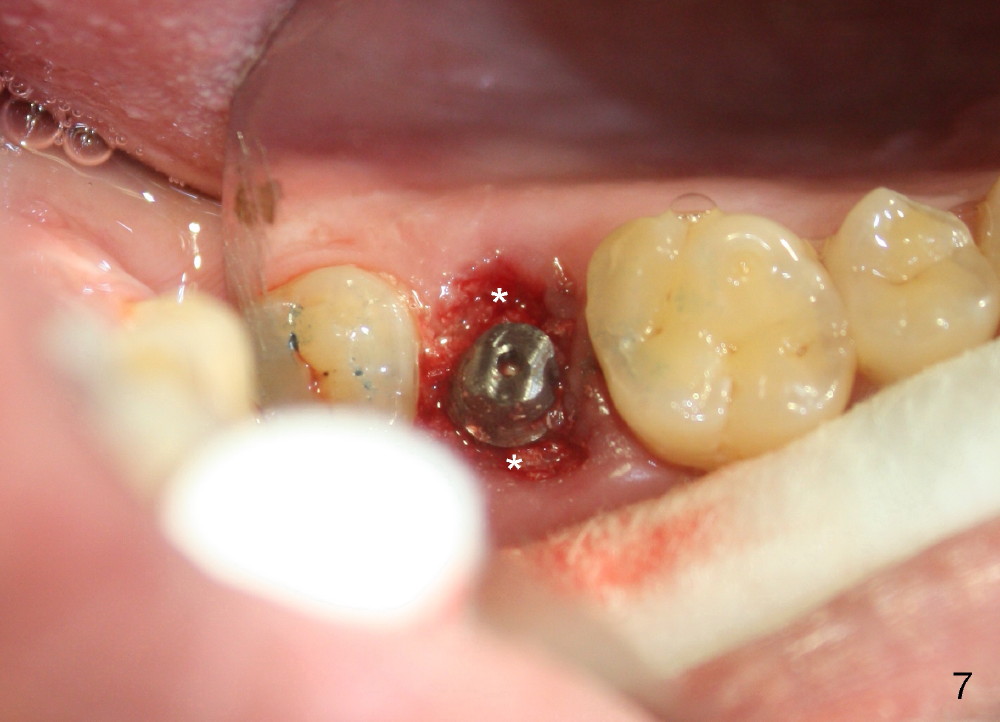

To prevent the narrow spaces from getting worse during osteointegration, an immediate provisional is to be fabricated. There is not enough occlusal clearance when the abutment is reduced ~1.5 mm. The abutment is removed; the implant is placed ~ 1 mm deeper with primary stability. Then the occlusal clearance is sufficient; the provisional is made. Mixture of autogenous bone, allograft and Osteogen is placed in the remaining buccal and lingual sockets (Fig.7 *). The provisional is temporarily cemented (Fig.8 P), which keeps the bone graft in place.